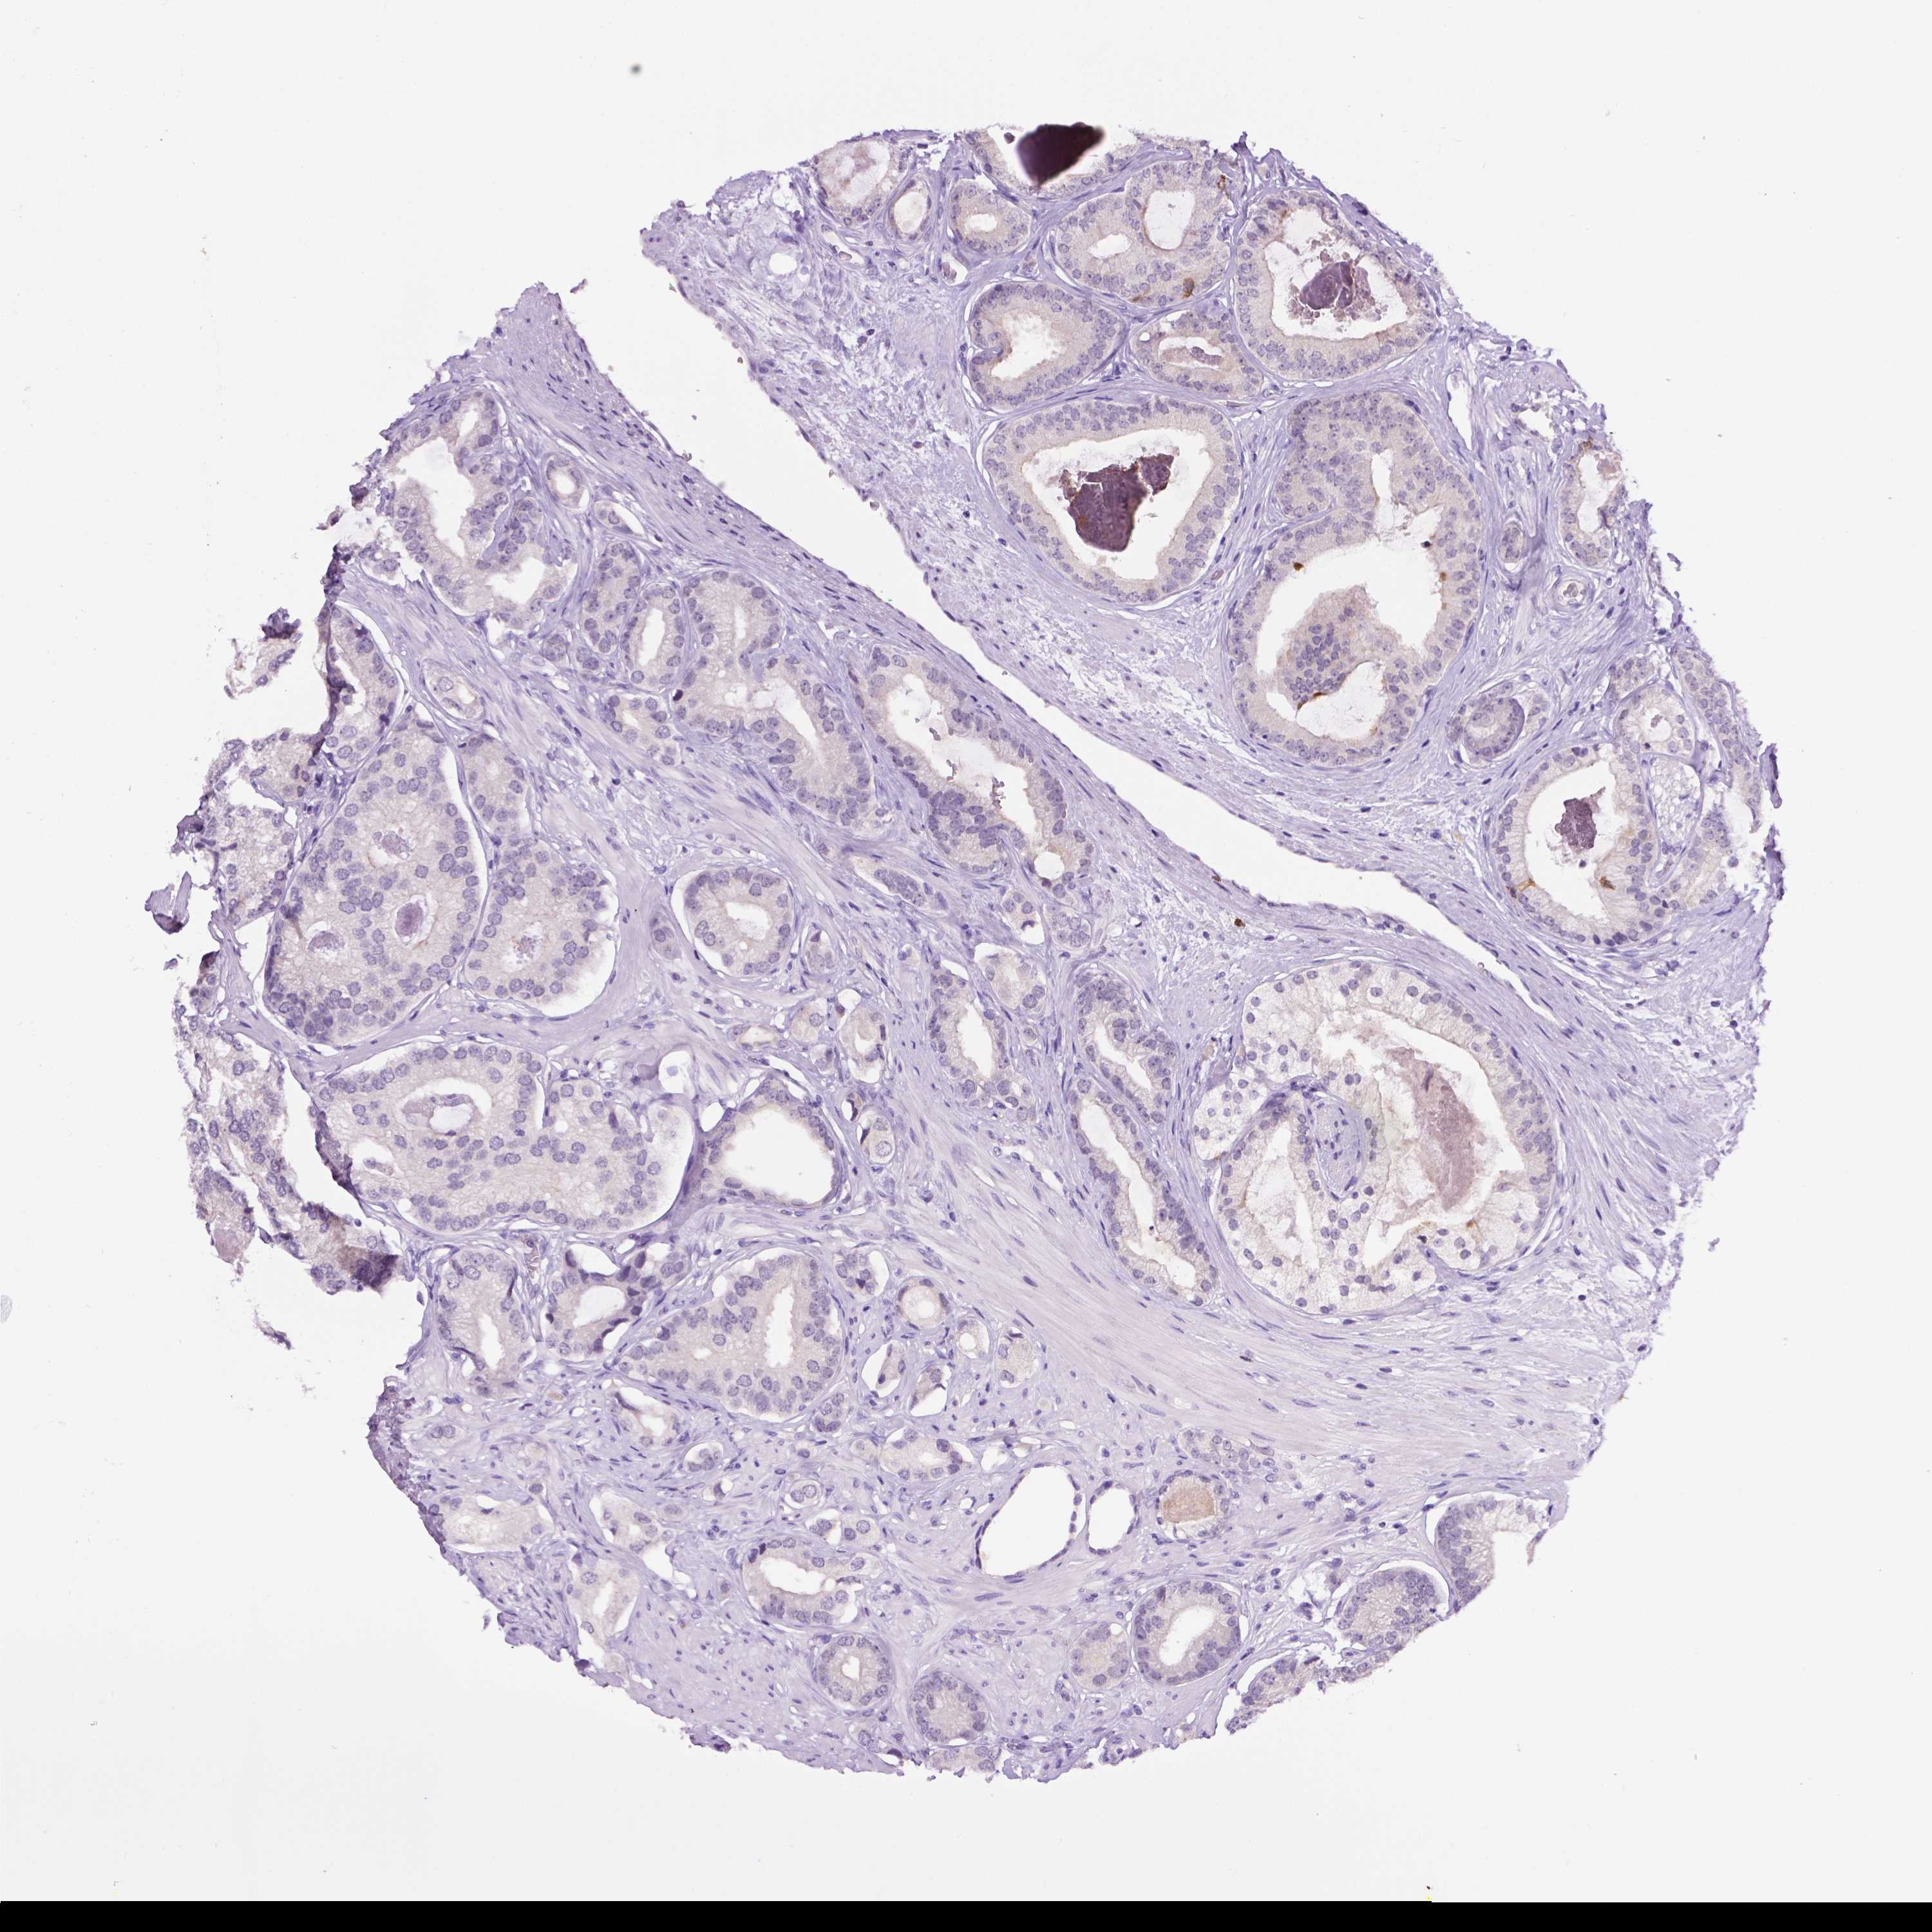

PROSTATE CANCER - Protein expressioni

A mouse-over function shows sample information and annotation data. Click on an image to view it in a full screen mode. Samples can be filtered based on level of antibody staining by selecting one or several of the following categories: high, medium, low and not detected. The assay and annotation is described here.

Note that samples used for immunohistochemistry by the Human Protein Atlas do not correspond to samples in the TCGA dataset.

Antibody stainingi

Antibody staining in the annotated cell types in the current human tissue is reported as not detected, low, medium, or high, based on conventional immunohistochemistry profiling in selected tissues. This score is based on the combination of the staining intensity and fraction of stained cells.

Each image is clickable and will lead to virtual microscopy that enables deeper exploration of all samples and also displays staining intensity scores, fraction scores and subcellular localization as well as patient and tissue information for each sample.

Antibody HPA069097

Staining

High

Medium

Low

Not detected

Intensity

Strong

Moderate

Weak

Negative

Quantity

>75%

75%-25%

<25%

None

Location

Nuclear

Cytoplasmic/membranous

Cytoplasmic/membranous,nuclear

Adenocarcinoma, High grade

Adenocarcinoma, Medium grade

Adenocarcinoma, Low grade